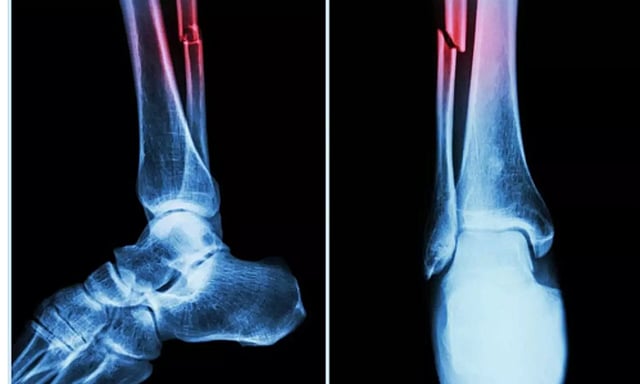

LONDON: The Covid-19 pandemic has had negative effects on bone tissue -- including both bone mineral density in the forearm and total bone mineral content, according to a study.

The study, published in the Journal of Orthopaedic Research, suggested that people with Covid‐19 may experience long‐term orthopaedic issues, such as decreased bone mass, increased fracture risk and other musculoskeletal complications.

In the study, mice who had Covid-19 showed significant bone loss. This loss decreased the bone mechanical strength and increased the risk of fractures.

The study suggested that the higher risk of fragility fractures, when a person falls from standing height or less, may be one of the underreported long-haul symptoms of Covid.